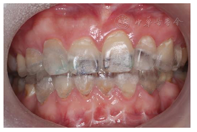

(1)面部检查:面部外形不对称,颏部居中,两侧口角高度不一致,面下1/3高度减小,两侧颧弓突度一致,下颌前突。中位笑线,上唇长度适中(图1)。(2)关节检查:颞颌关节:弹响(-),杂音(-),疼痛(-)。开口度正常,开口型有偏斜,肌肉触诊压痛:右侧上颌结节(+)、左侧上颌结节(++)、双侧翼内肌(+),其他肌肉及颞下颌关节区未诉异常,关节载荷实验无任何紧张和疼痛不适。(3)口内检查:上下颌牙中线较面中线向右偏斜,前后牙广泛不均匀磨耗,前牙磨耗后呈刃状;14、21、22、23及下颌牙唇颊侧颈部见釉质缺损,部分牙本质暴露,呈黄褐色,少量白垩色;44牙见开髓孔,表面暂封。12缺失,缺失牙间隙无。全口牙龈色形质未见异常,11牙、21牙唇侧牙龈龈缘高度不一致,21牙较11牙龈缘高约3mm。全口口腔卫生状况良好,菌斑、软垢少量,未及牙石及牙周袋。咬合检查:11-14牙与对颌牙反

,21牙与31、31牙对刃,左侧尖牙至前磨牙深覆盖,

曲线不平(图2,图3)。(4)影像学检查: